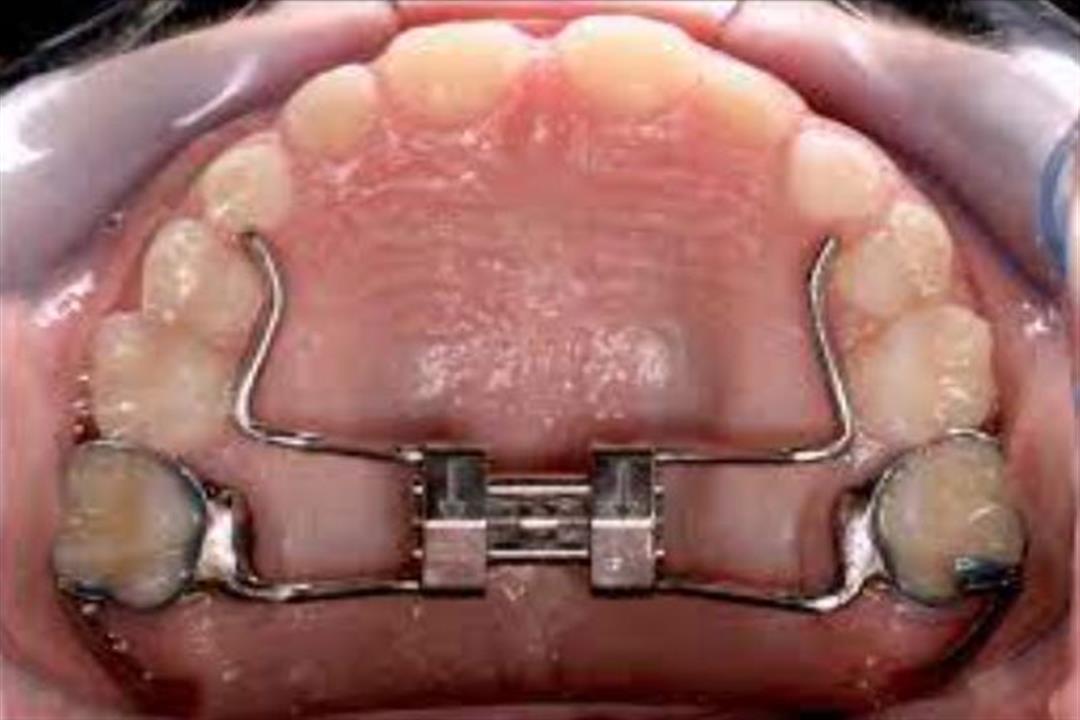

2-أجهزة توسيع الفك السريعة

يحتوي جهاز توسيع الفك الثابت على أشرطة مصممة لتتلائم بشكل سريع مع الأضراس الخلفية الفردية، ولكن يجب الحذر جيدًا حول التعليمات الواجب تنفيذها تحت إشراف الطبيب المختص لتجنب التعرض لأي مضاعفات صحية.

3-جهاز اللولب الرباعي

هذا النوع من الجهاز ثابت ويتم أيضًا ربطه بالضروس الخلفية في الفك حيث يتم تركيبه في وضع مضغوط ويفتح بلطف من تلقاء نفسه ولا يتطلب أي تدخل يدوي.